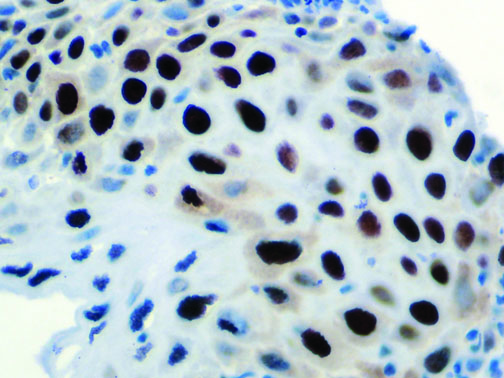

Clinical and laboratory manifestations of HLH include fever, enlarged liver and/or spleen, neurologic dysfunction, coagulopathy, liver dysfunction, cytopenias (i.e., low levels of erythrocytes, leukocytes, and/or platelets), hypertriglyceridemia, hyperferritinemia, hemophagocytosis, and eventually diminished NK cell activity as the immune system becomes progressively paralyzed. HLH can be familial (primary HLH) or secondary to another disease process (sHLH), such as rheumatic disease, in which it is referred to as macrophage activation syndrome (MAS, characterized by elevated ferritin).